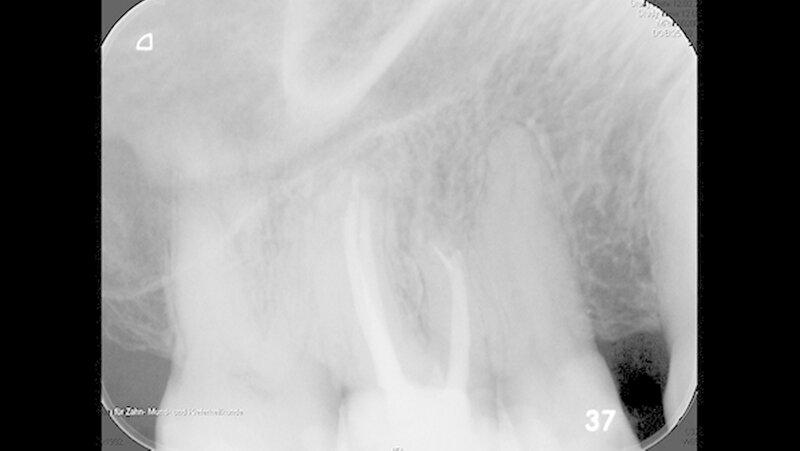

Er berichtete, dass an diesem Zahn ungefähr ein Jahr zuvor eine Wurzelkanalbehandlung alio loco durchgeführt worden war. Das angefertigte Röntgenbild (Abbildung 1) zeigte eine apikale Aufhellung und ein frakturiertes Wurzelkanalinstrument, das vermutlich über den Apex des mesiobukkalen Wurzelkanals herausragte. Die Füllung aller vier Wurzelkanäle erschien röntgendicht, wandständig und ohne Zeichen von Porositäten oder Lufteinschlüssen.